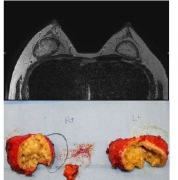

自体脂肪隆胸失败案例分析

隆胸手术简直是小胸妹子的福音,它让小胸妹子在后天拥有自然真实的美傲挺胸,在众多隆胸手术中,自体脂肪隆胸